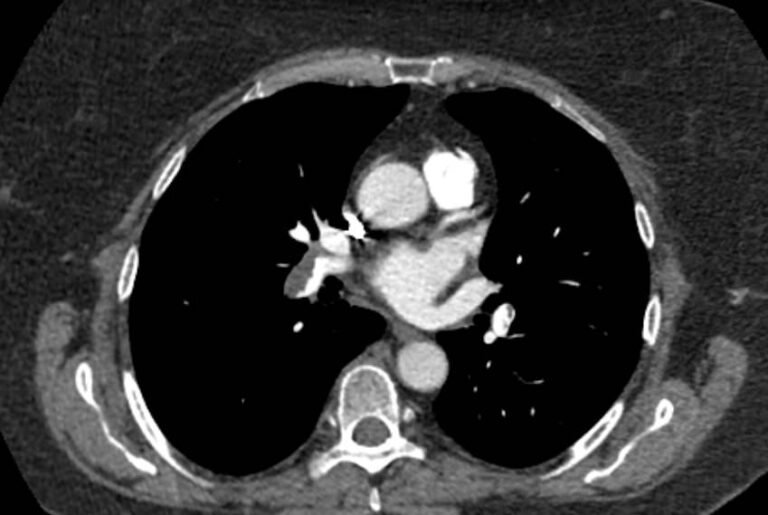

Тромбоэмболия легочной артерии характеризуется закупоркой просвета легочной артерии (либо самого легочного ствола, либо более мелких ветвей) тромбом. Тромб может образоваться в глубоких венах нижних конечностей, малого таза, часто после травм, операций, родов, а также в правом предсердии (на фоне нарушений сердечного ритма) и с током крови попадает в систему легочной артерии.

ТЭЛА может стать причиной внезапной смерти, а в некоторых случаях может приобретать хронический характер, когда тромбы малого размера закупоривают мелкие легочные артерии. В любом случае своевременная диагностика ТЭЛА может спасти жизнь больного.

Наиболее информативным, при этом быстрым и неинвазивным (то есть без вмешательства в организм пациента), методом диагностики патологии легочной артерии является мультиспиральная компьютерная томография (КТ-ангиография). Методика основана на использовании рентгеновского излучения в сочетании с цифровой обработкой данных для получения трехмерных изображений сосудистой системы.

Для визуализации кровеносных сосудов в обязательном порядке применяется контрастное усиление. Для этого в вену пациента вводится йодсодержащий контрастный препарат, который попадая в кровоток активно поглощает рентгеновские лучи и ярко контрастирует сосудистую систему, в том числе легочной артерии, на фоне окружающих тканей. Использование контраста дает возможность визуализировать даже мелкие артерии и выявить патологию.

• ТЭЛА (тромбоэмболия легочной артерии);